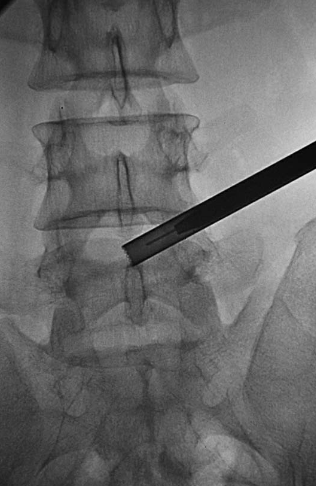

双针技术(图13):调整勺状针的勺状面方向,向脚端、向背侧;在勺状针内,置入笔尖针达突出髓核内。

图13 双针技术A.前后位透视笔尖针针尖达第三靶点;B.侧位透视笔尖针针尖达L5椎体后缘(突出髓核内)。

造影与染色(图14):注入突出物内2ml碘海醇和亚甲蓝的混合液(4∶1)进行造影与染色。

图14造影与染色A.前后位透视;B.侧位透视